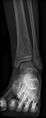

PA view of the left distal tibia showing a lytic lesion in the distal metaphysis with a narrow zone of transition more caudally with a faint sclerotic rim and a wide zone of transition more cephalad. Periostial reaction along the medial cortex indicates an aggressive lesion. Neoplasm such as Ewing sarcoma and osteomyelitis could both have this plain radiographic appearance. Staphylococcus was recovered at surgery.